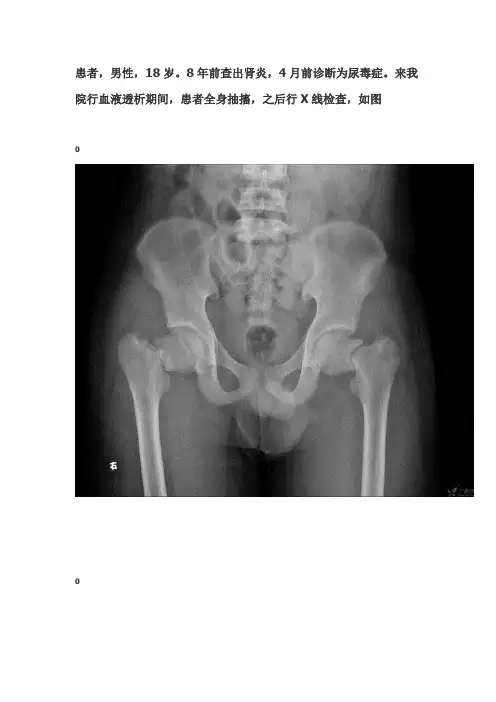

患者,男性,18岁。

8年前查出肾炎,4月前诊断为尿毒症。

来我院行血液透析期间,患者全身抽搐,之后行X线检查,如图诊断典型肾性骨病依据:1、男性,18岁。

来我院行血液透析期间,患者全身抽搐。

2、平片:双侧股骨颈骨折,股骨干颈角缩小,左肱骨外科颈骨折,左尺桡骨弯曲。

上述骨骼均显示密度下降。